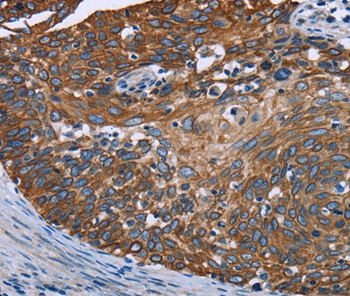

Immunohistochemical analysis of paraffin-embedded Human lung cancer tissue using #36548 at dilution 1/40.

Immunohistochemical analysis of paraffin-embedded Human cervical cancer tissue using #36548 at dilution 1/40.